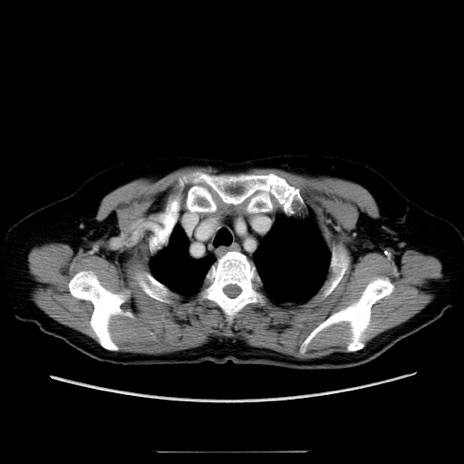

症例5(横断像)

【症例】70歳代女性

【主訴】お腹が張る

【現病歴】1週間くらい前から腹部膨満の自覚あり。昨日夜から増悪したため、本日救急外来受診。

【身体所見】意識清明、BT 36.5℃、BP 165/106mmHg、HR 80bpm、SpO2 98%、腹部:膨満、軟、自発痛・圧痛なし、触診にて不快感あり、腸蠕動音:減弱

【データ】WBC 12600、CRP 1.04